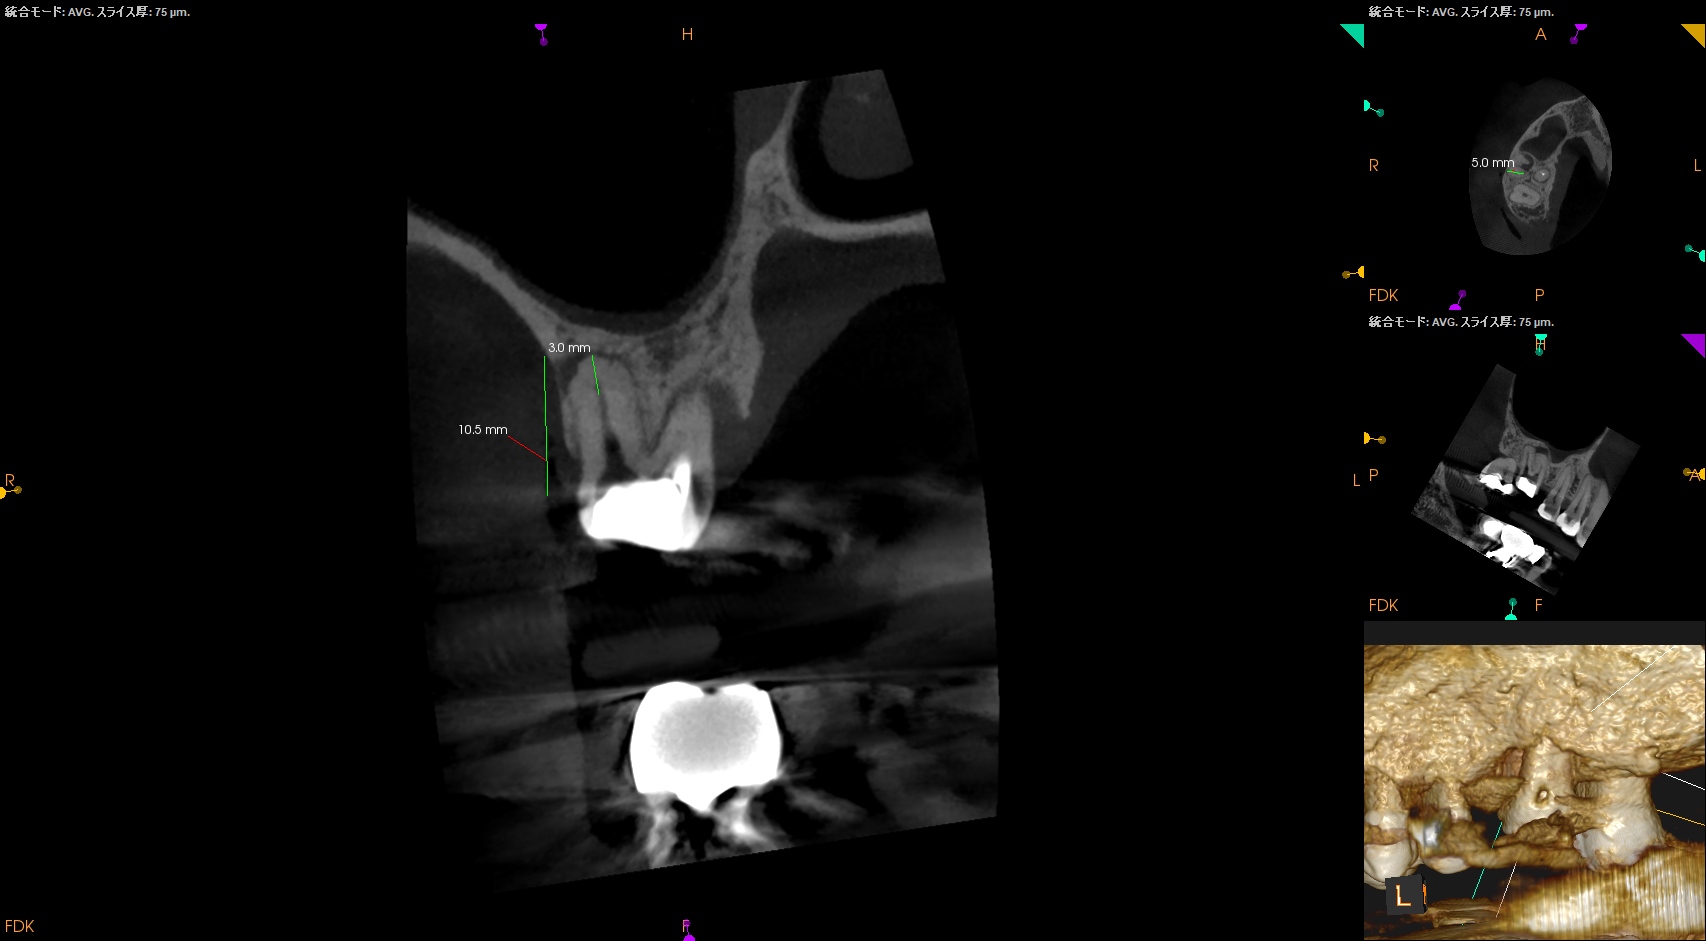

MB,DBのApicoectomyは

MB

CEJよりも12mm下方にMBのApexがあり、

そこを3mm切断するには6.4mmの切断幅が必要である。

DB

DBはCEJよりも10.5mm下方にApexがあり、そこを3mmで切断するには5mmの頬舌的幅が必要で1根管なことからここはEasyだ。